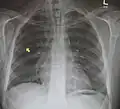

Pneumomediastinum is uncommon and occurs when air leaks into the mediastinum. The diagnosis can be confirmed via chest X-ray showing a radiolucent outline around the heart and mediastinum or via CT scanning of the thorax.

Pneumomediastinum and right sided pneumothorax post first rib fracture in a mountain biking accident. -

Pneumomediastinum with angel wing sign[15] -